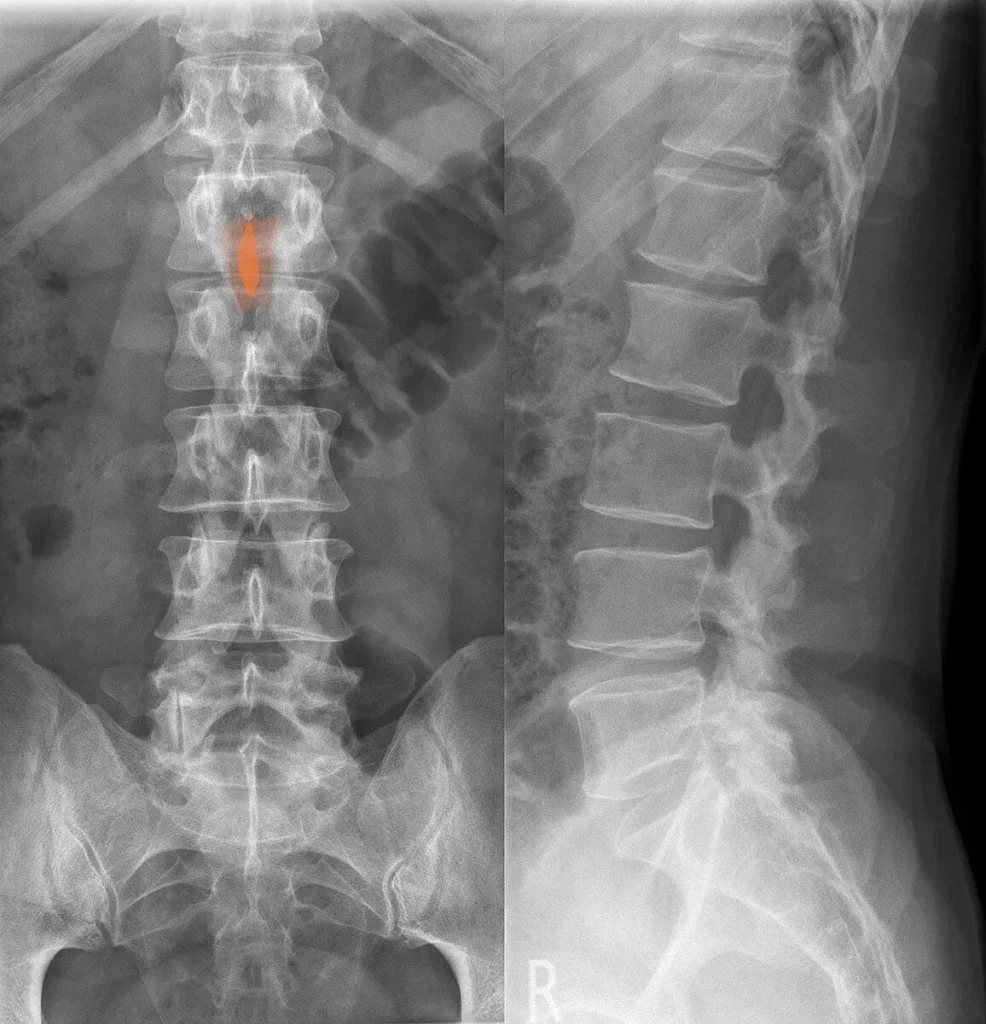

X-Ray

X-rays are the most accessible initial imaging tool for bone spur evaluation. They clearly show osteophyte formation at vertebral margins, disc space narrowing, and facet joint hypertrophy. X-rays are used as the first step to assess the extent of bony degeneration and determine whether more detailed imaging is needed.

MRI: The Gold Standard

MRI provides the most complete picture of spinal bone spur impact. It visualizes not only the osteophytes themselves but also the degree of neural foramen narrowing, the extent of spinal cord or nerve root compression, and the condition of the surrounding discs, ligaments, and soft tissues. MRI is essential for surgical planning and for correlating imaging findings with the patient’s specific symptoms.

CT Scan

CT scanning provides superior detail for bony anatomy compared to MRI and is particularly useful for characterizing the size, shape, and precise location of bone spurs before surgery. CT myelography, which involves injecting contrast into the spinal fluid, provides even more detailed visualization of nerve root and cord compression in complex cases.